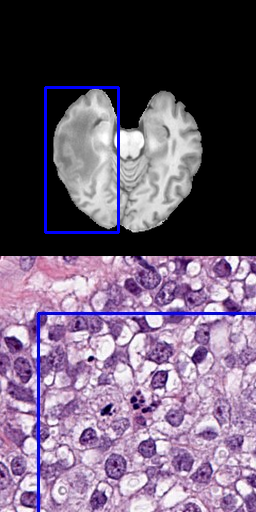

One approach is to use several positive points as input data that represent the goal label [8]. Using points as input is a precise method, allowing to preserve fine segmentation details but requires more annotation effort. When large areas are annotated, this is especially problematic. Figure 3 shows samples for using 3, 10, 50 or 100 points for the radiology and pathology data.

Refer to caption

(a) 3 positive points

(b) 10 positive points

(c) 50 positive points

(d) 100 positive points

Figure 3: Results for different number of positive points without bounding box